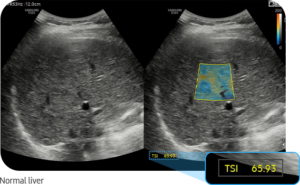

Die moderne Ultraschall-Elastographie ermöglicht eine präzise und nicht-invasive Beurteilung der Lebergesundheit. Dabei können sowohl der Grad einer Verfettung (Steatose) als auch strukturelle Veränderungen wie eine Fibrose oder beginnende Zirrhose frühzeitig erkannt werden.

Je höher die gemessene Gewebesteifigkeit, desto wahrscheinlicher ist eine fortgeschrittene Lebererkrankung. Die Messwerte werden in Kilopascal (kPa) angegeben und erlauben eine Einschätzung des Fibrosegrades.